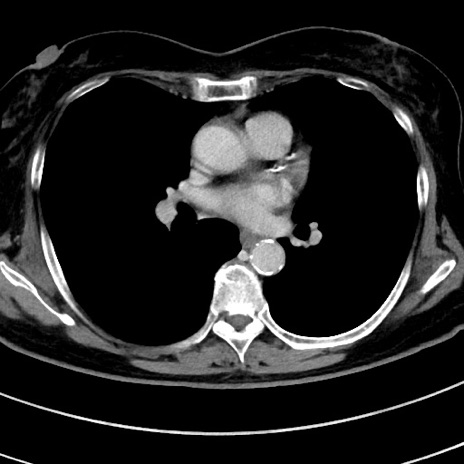

冠状断像

【症例】 60歳代女性

【主訴】むかつき、みぞおちの痛み

【現病歴】3日前よりむかつきがあり、食事がとれない。

【既往歴】糖尿病

【身体所見】発熱なし、心窩部圧痛軽度あるも、腹膜刺激症状なし。

【データ】WBC 7400、CRP 1.92